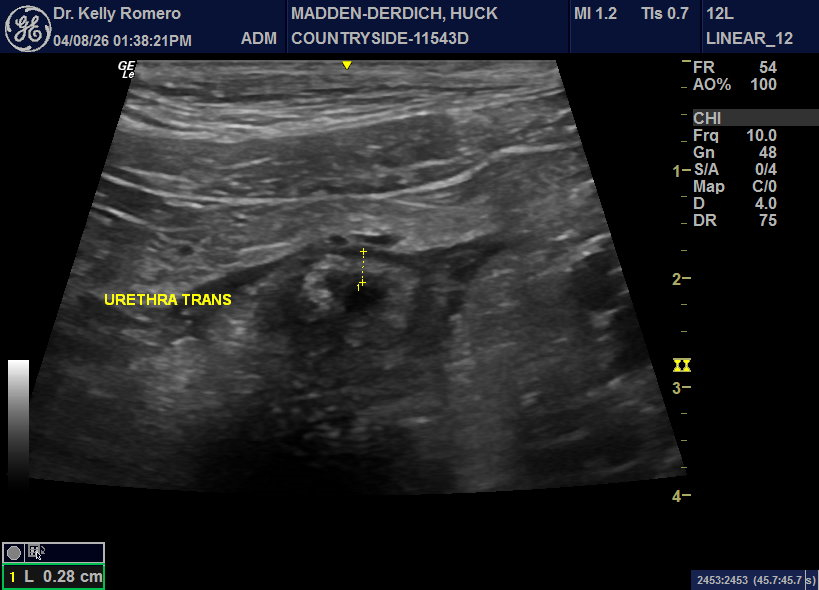

6 year old MI Goldendoodle owner noticed about 15 drops of blood in the kitchen coming from patient’s penis. He had not been straining to urinate. pcDVM started patient on Enrofloxacin 5 days ago and patient has not had any recurrence. Owner had declined a UA. I’m concerned about prostatitis, but also could not tell if I’m seeing normal prostatic overlap into urethra or if I should be concerned about a urethral mass. Our current plan is to finish enro, neuter and follow up if any recurrence (Braf test, recheck ultrasound). Thoughts?

Looks like overlap. The appearance of the prostate is more likely age-related benign cystic prostatic hyperplasia than prostatitis. Perfect plan that you have for this patient.